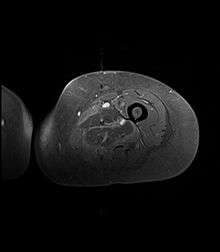

Creatine kinase may be normal or increased probably depending upon the stage of the condition when sampling is undertaken. ESR is elevated. Planar X-ray reveals soft tissue swelling and may potentially show gas within necrotic muscle, Bone scan may show non specific uptake later in the course. CT shows muscle oedema with preserved tissue planes (non-contrast enhancing). MRI is the exam of choice and shows increased signal on T2 weighted images within areas of muscle oedema. Contrast enhancement is helpful but must be weighed against the risk of Nephrogenic Systemic Fibrosis as many diabetics have underlying renal insufficiency. Arteriography reveals large and medium vessel arteriosclerosis occasionally with dye within the area of tissue infarction . Electromyography shows non specific focal changes.